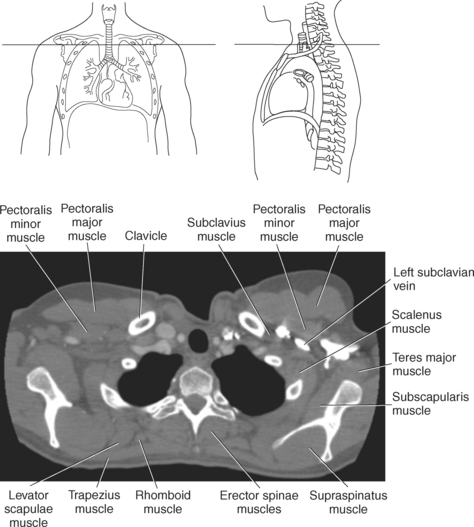

Muscles of the anterior and lateral thoracic region are pectoralis major, subclavius, pectoralis minor, and serratus anterior. Muscles associated with the movement of the upper extremity such as the pectoralis, subclavius, and serratus anterior can also function as accessory muscles for respiration (Figure 6.114 and Table 6.4). For example, the pectoralis muscles (major and minor), located on the anterior surface of the chest, primarily aid in the movement of the upper limb, but the pectoralis major muscle can also act to expand the thoracic cavity on deep inspiration (Figures 6.115 and 6.116). The subclavius, a small triangular-shaped muscle located between the clavicle and first rib acts alone to stabilize the clavicle and depress the shoulder. However, conjointly with the pectoralis muscles, the subclavius muscles act to raise the ribs, drawing them upward and expanding the chest, thus becoming important agents in forced inspiration. Additionally, the serratus anterior muscles aid in respiration. The serratus (sawlike) anterior muscle is visualized on the lateral border of the thorax. It extends from the medial border of the scapula to the lateral surface of the first rib through eighth ribs. The primary action of the serratus anterior muscle is to laterally rotate and protract the scapula. It can, however assist in raising the ribs for inspiration (Figure 6.114; see also Chapter 9).